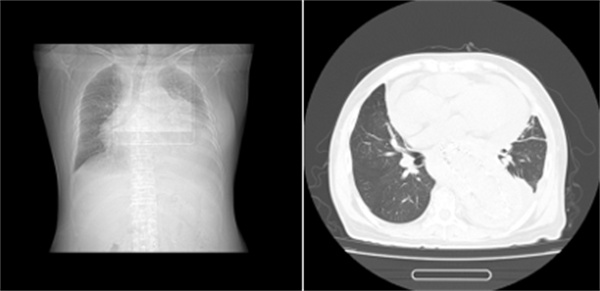

图表1一位长期透析不充分的女性患者

尿毒症毒素会让心包的毛细血管壁变得“千疮百孔”,另外还有尿毒症相关心肌病等问题,毛细血管通透性增加,导致血管里的液体和蛋白质渗出来,堆积在心包腔里。这就像在心脏周围倒了一杯“毒水”,引发了无菌性炎症。

如果水分的摄入(喝水、喝汤、吃水果)没有得到严格控制,多余的水分就会滞留在体内。这部分水不仅会导致腿肿、脚肿、血压高,还会寻找各种缝隙钻进去,会渗到组织间隙,同样也会漏到心包腔里,形成积液。

尿毒症患者各种原因容易出现低蛋白血症。血液中的蛋白质就像“海绵”,能把水分牢牢吸附在血管里。一旦蛋白质减少,“海绵”吸水的功能就下降了,血管里的水分就会跑到血管外,心包就是其中一个“落脚点”。

也就是我们常说的“围透析期”,通常发生在刚开始透析,或者透析不充分的患者身上透析不充分,我们图中第二例患者就是一位未及时开始透析的终末期透析患者。如果透析次数不够、时间不足,毒素清除得不够理想,依然会持续刺激心包。